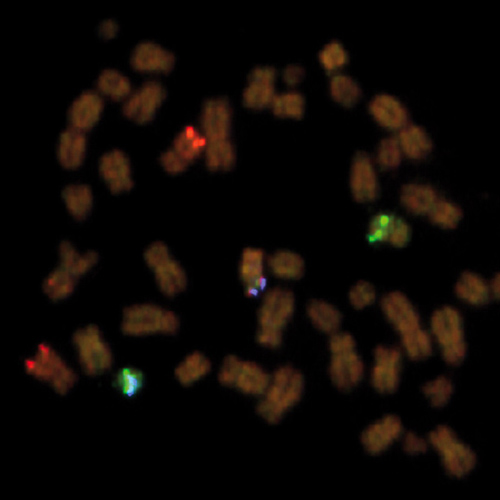

KBI-10105

6q21 / SE 6